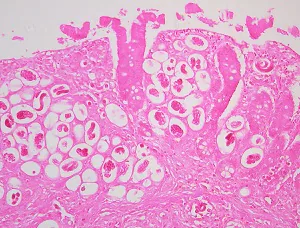

In humans, Angiostrongylus eggs and larvae remain sequestered in tissues and do not appear to be excreted in stool. A. costaricensis infections are predominantly abdominal; both eggs and larvae (occasionally adult worms) can be identified in biopsy or surgical specimens of intestinal tissue, where the eggs and larvae typically are engulfed in giant cells and/or granulomas.

The larvae of A. costaricensis in tissue sections need to be distinguished from larvae of Strongyloides . A. costaricensis first-stage (L1) larvae tend to be slightly smaller in diameter than S. stercoralis third-stage (L3) larvae and have single lateral alae, whereas S. stercoraliss L3 larvae have minute double lateral alae. The alae can be difficult to discern in most histologic sections. However, the presence of granulomas containing thin-shelled eggs and/or larvae generally serves to distinguish A. costaricensis infections from Strongyloides infections.